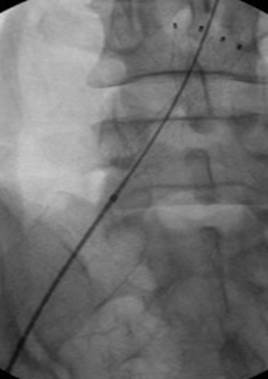

Paciente de 44 años de edad y sexo femenino con TVP iliofemoral izquierda masiva tras histerectomía por varios fibromas. Venograma en posición decúbito supino de la vena femoral común izquierda antes de la inserción del filtro de vena cava temporal que indica un trombo que protruye de la vena ilíaca común izquierda.

Cavograma tras colocación del filtro temporal en la vena cava inferior donde se muestra el trombo que protruye y se extiende desde la vena ilíaca común izquierda.

Venograma en posición decúbito prono de la vena femoral izquierda donde se muestra un trombo masivo dentro del lumen de la vena.

Venograma en posición decúbito prono donde se muestra un trombo que obstruye las venas ilíaca y femoral.

Venografía de la vena femoral tras trombectomía fármaco-mecánica (PMT) mediante la técnica Power Pulse Delivery (se usaron 15 ml de una solución de 50 mg de tPA  en 500 ml de solución salina natural) seguida por 2 pasadas con el catéter DVX de AngioJet.

Venografía en posición decúbito supino tras introducir 2 veces el catéter DVX de AngioJet. Vena ilíaca externa y vena femoral común del paciente. Estenosis severa de la vena ilíaca común.

Venografía de la vena ilíaca común izquierda tras colocar un stent de 12 x 100 mm utilizando un ATP de 10 x 60 mm. Duración total de la intervención: 105 minutos.

Venografía final tras la trombectomía fármaco-mecánica (PMT), la colocación de un stent en la vena ilíaca común y la retirada del filtro de VCI.

Karlo Novacic, Departamento de Radiología Intervencionista, Hospital Clínico Merkur, Zagreb, Croacia (2013).